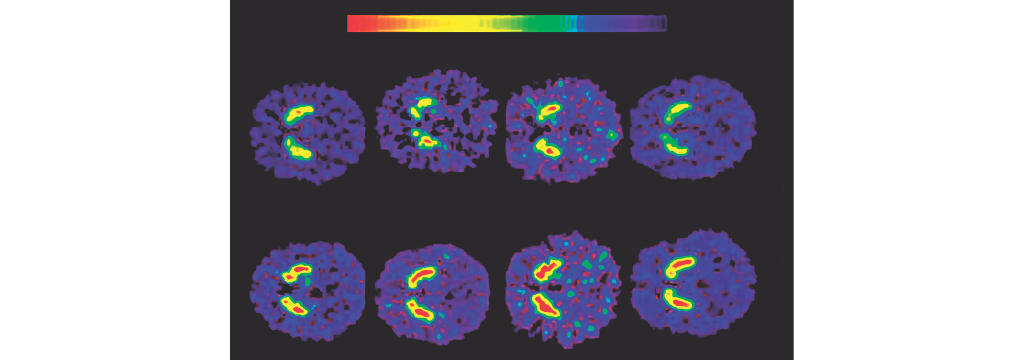

Según un estudio de 2022 del Hospital General de Massachusetts, la droga empieza a generar un deterioro en la respiración unos cuatro minutos antes de que lo adviertan los sistemas de alerta del organismo. Fotografía: Drug Enforcement Administration (DEA)